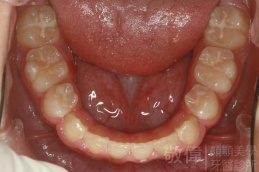

矯正前-上   矯正前-下

矯正後-上   矯正後-下

<個案說明>

戽斗(學名第三級咬合 class III)矯正之後,戽斗的樣子就比較沒有了。最主要的改變是在牙齒的咬合。從側面比較,治療前、治療後的臉型 可更明顯看出來 戽斗的感覺 減少了很多。